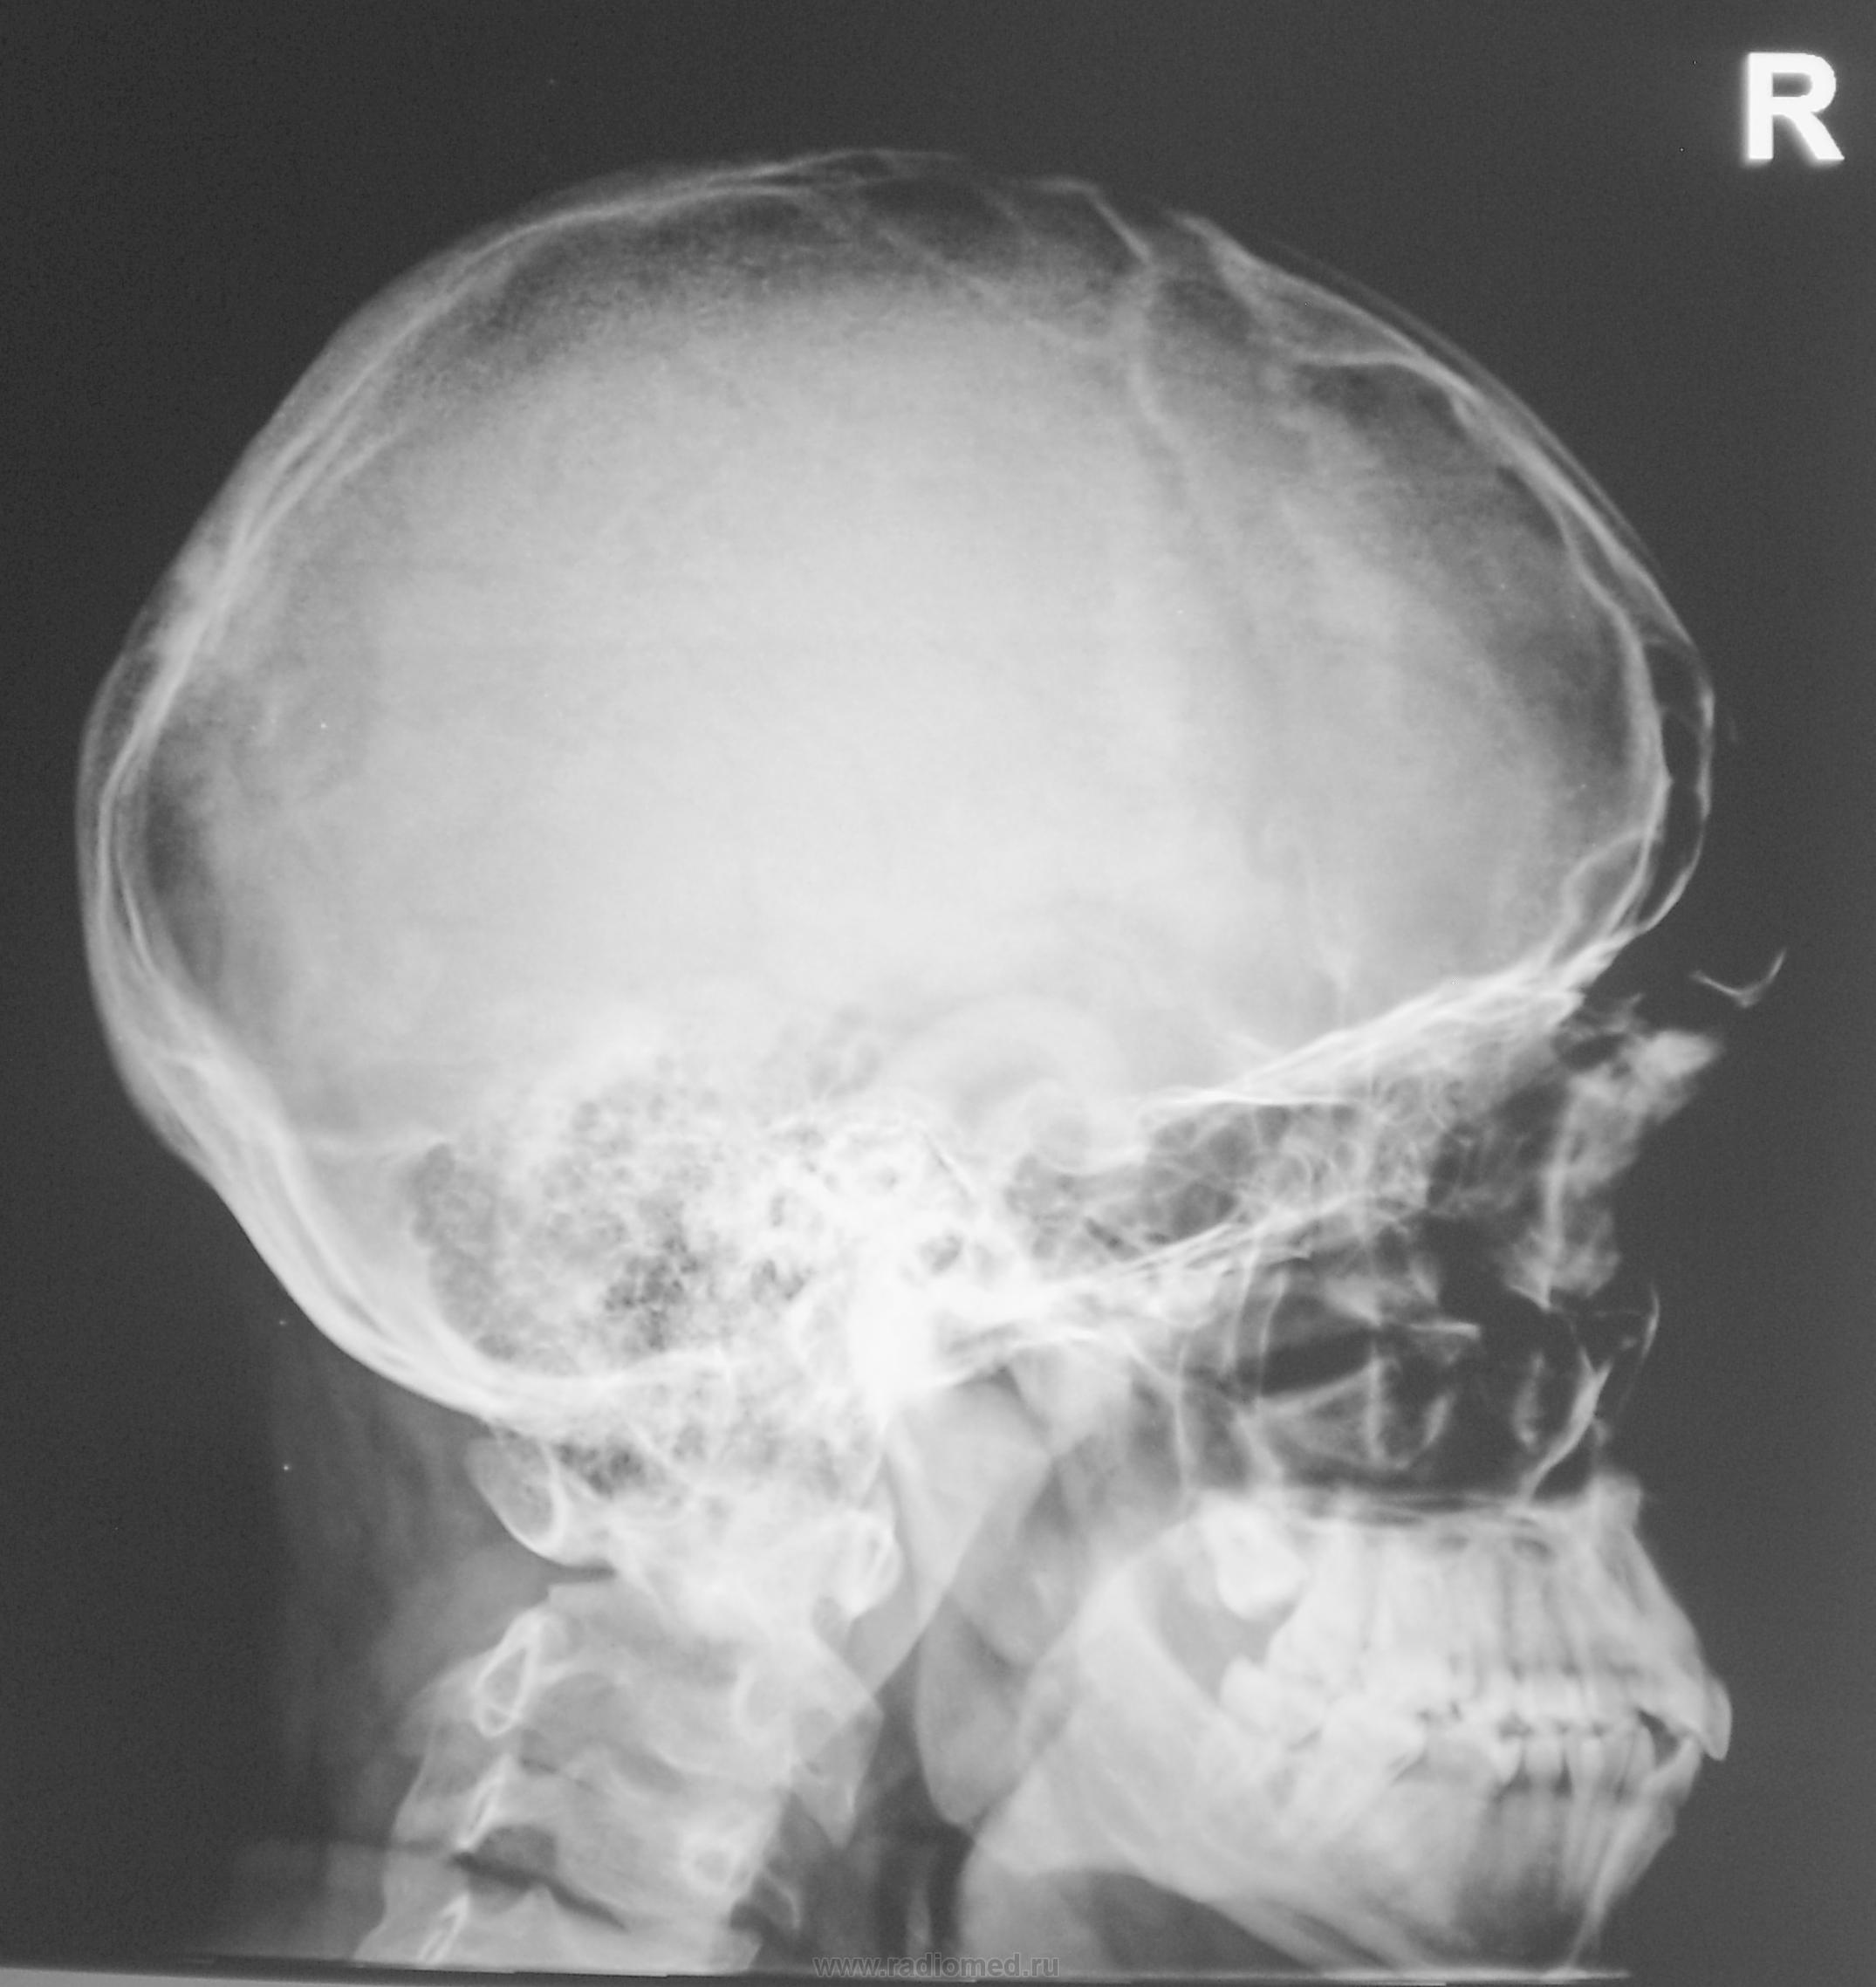

Какие мнения будут по поводу черепа уважаемые коллеги?

Не видно четко контуров верхнего края теменной области и лобных пазух по передней поверхности, хотя мягкотканный компонент не выражен-деструкция костной ткани в результате миеломной болезни?

Локальный эндокраниоз: обызвествление диафрагмы турецкого седла.

Лобных пазух таки не видно. Помнится что-то подобное упоминалось у Сусловой в разделе гистиоцитозы. Жаль книга на работе, но возможно есть что-либо в инете? Но миеломную исключать нельзя.

Чудесно, ничего и нигде не меняется. Остаюсь пока при своем-миеломная или гистиоцитоз. Интересно мнение рентгенологов, работающих с гематологическими больными.

Сам пациент о "дыре" ничего не знает, не знает и участковый врач. Экспозиция для снимка была адекватная, потом сделали снимок на "мягком" режиме, но картинка стабильная - дыра.

Дыра есть, но может в детстве в лоб кто-то заехал?

Травмы не было.

А на ощупь дыра чуствуется.

Но чётких признаков деструкции не видно.